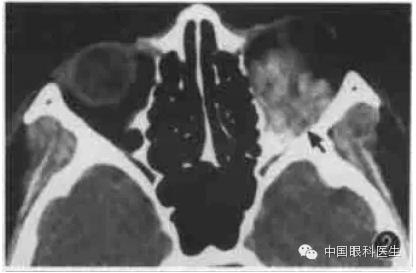

4.压颈检查

眶内静脉曲张常规CT扫描时多不显影,或仅显示小部分病变,欲观察病变全部范围可行颈部加压检查(图1,图2)。将血压计袋缠于患者颈部,摆好位置,加压至5.33kPa(高于静脉压),再行扫描检查,扫描完毕后立即将气囊放松。

图1左眶静脉曲张,平扫CT显示左眶后少许软组织密度(箭头)

图2同例静脉曲张加压后CT显示左眼球明显出土,球后出现巨大高密度软组织块影(箭头)